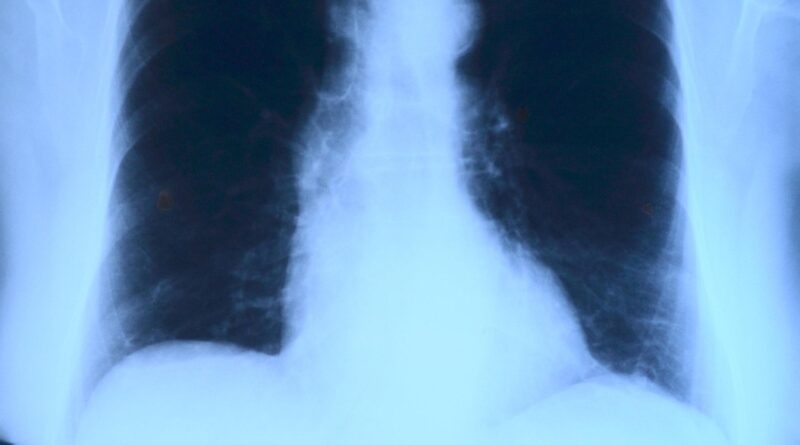

Tuberkuloza je zarazna bolest koju izaziva bakterija Mycobacterium tuberculosis. Najčešće pogađa pluća, ali može zahvatiti i druge organe, uključujući mozak, bubrege i kičmu.

Bez adekvatnog lečenja, tuberkuloza može izazvati trajna oštećenja pluća i druge ozbiljne komplikacije, uključujući meningitis ili otkazivanje organa. Međutim, dobra vest je da je bolest izlečiva.